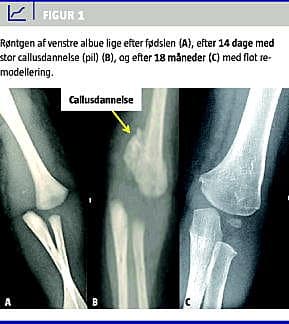

Sygehistorien omhandler en pige, der var født ved planlagt sectio som nummer et af en. Under forløsningen blev der trukket hårdt i patientens venstre overekstremitet. Ved den efterfølgende undersøgelse var armen pseudoparalytisk med blålig misfarvning af albuen, som virkede løs og smertefuld. Røntgen af venstre overekstremitet blev initialt tolket som en posteromedial albueluksation (Figur 1 A), men ved ny gennemgang stillede man diagnosen TDHE. Patienten blev behandlet med en gipsskinne i 14 dage uden forsøg på reposition. Ved gipsfjernelsen var der hævelse og bevægeindskrænkning ved albuen, men ingen palpationsømhed. Røntgenundersøgelse viste callusdannelse (Figur 1B). Ved kontrol efter seks uger var der fortsat nogen hævelse ved venstre albue, men ingen palpationssmerter og kun beskeden begrænsning af albueflektionen. Efter otte og 18 måneder var funktionen i albuen normal, og sidste røntgenkontrol efter 18 måneder viste, at epifysiolysen var remodelleret til en god stilling (Figur 1C).

Diagnosen stilles ved det klassiske kliniske billede med hævelse, smerter, strepitus og pseudoparalyse af den afficerede arm [1, 2]. Olecranon bevarer sin triangulære relation med humerusepikondylerne. Røntgen vil bekræfte diagnosen, men kan mistolkes som en posteromedial luksation af albuen [1, 3, 4]. Radiologisk er relationen mellem radius og ulna bevaret og ved TDHE med medial og posteromedial dislokation peger længdeaksen gennem radius mod midterste del af humerusmetafysen (Figur 1). Traumatisk albueluksation er ikke kendt eller beskrevet i litteraturen hos børn under fire år [1], men i tvivlstilfælde kan ultralyd- eller magnetisk resonans-skanning foretages [1-5].